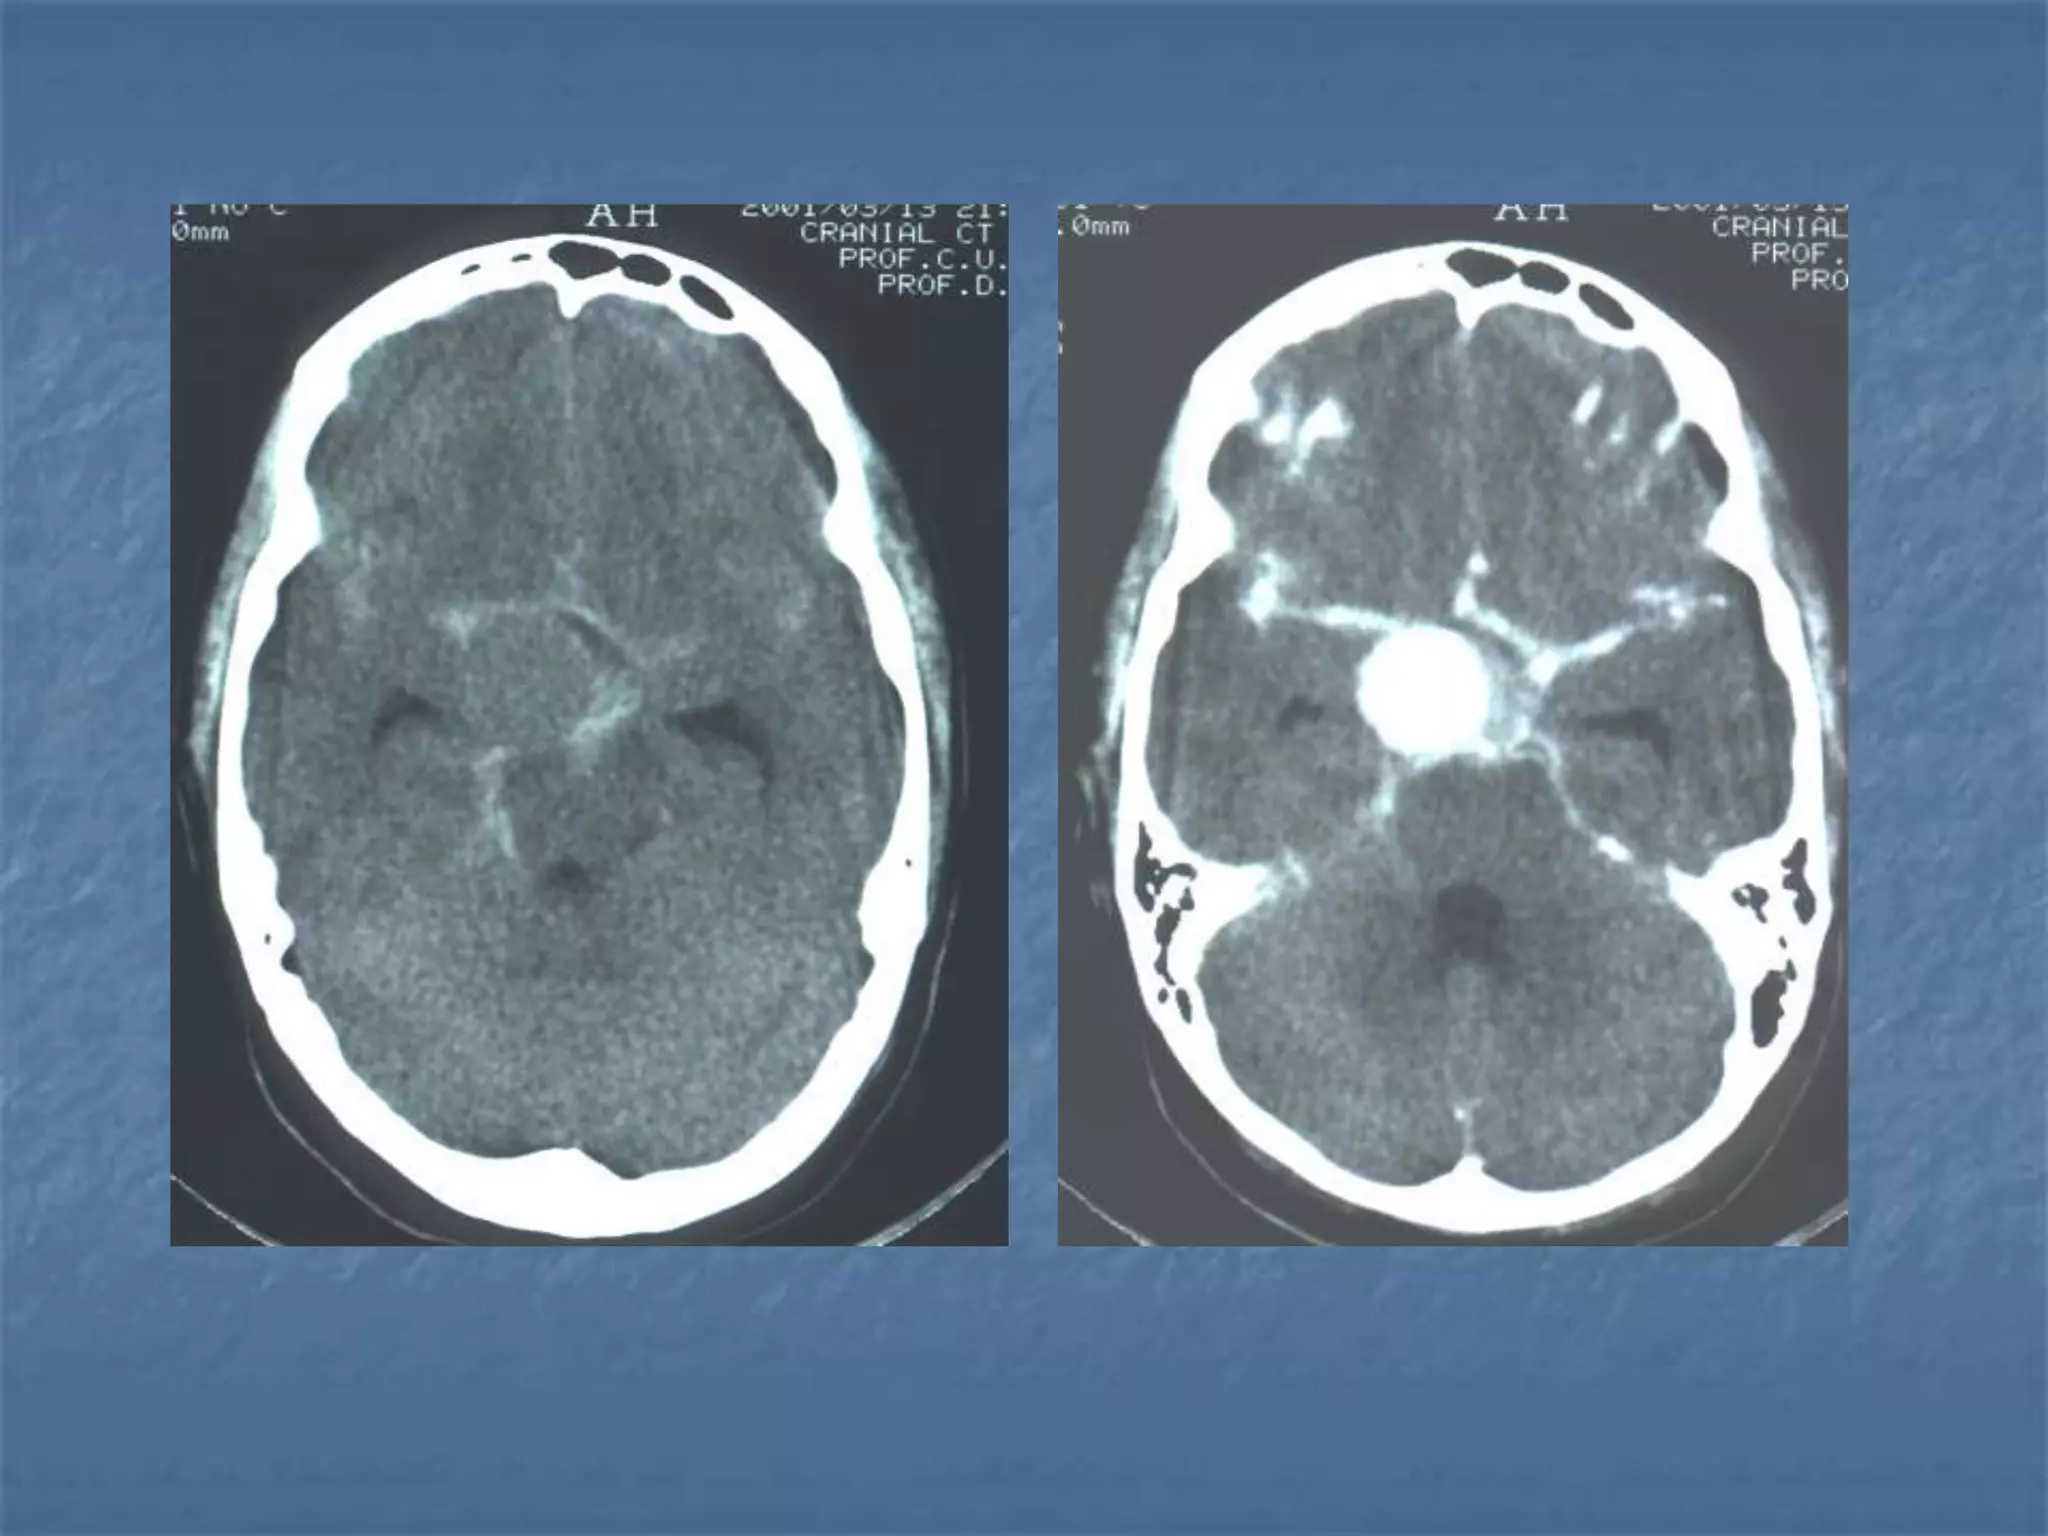

Subarachnoid hemorrhage

 CT is currently the imaging modality of choice because

of its high sensitivity for the detection of subarachnoid

hemorrhage. CT is most sensitive for acute

subarachnoid hemorrhage. After a period of days to

weeks CT becomes much less sensitive as blood is

resorbed from the CSF. If there is a strong clinical

indication, LP may be warranted despite a negative CT

since small bleeds can be unapparent on imaging.

On CT, a subarachnoid hemorrhage appears as high

density within sulci and cisterns. The insular regions

and basilar cisterns should be carefully scrutinized for

subtle signs of subarachnoid hemorrhage.

Subarachnoid hemorrhage may have associated

intraventricular hemorrhage and hydrocephalus.

